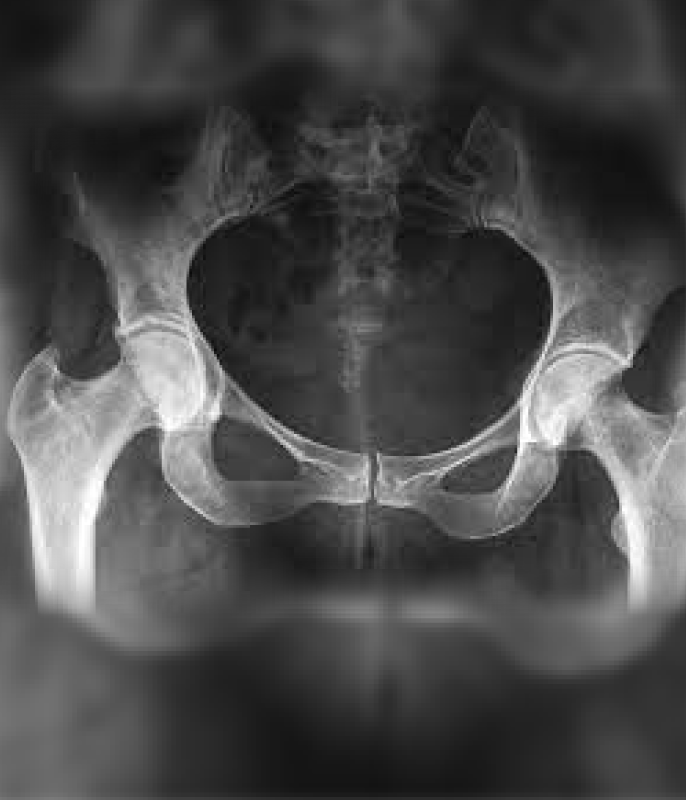

Es una patología común en el adulto joven deportista que cada vez está tomando más relevancia y que se caracteriza por una inadecuada relación femoroacetabular, con una clínica dolorosa e incapacitante de larga evolución, que puede simular otras patologías de la cadera, motivo por el cual, se debe realizar una anamnesis y una exhaustiva exploración física que nos oriente hacia esta patología, confirmando la sospecha diagnóstica mediante pruebas complementarias como la radiografía de pelvis y la resonancia magnética (RM). El tratamiento, en general, es quirúrgico. Debemos realizar un diagnóstico temprano ya que es una causa de artrosis precoz en el adulto joven.